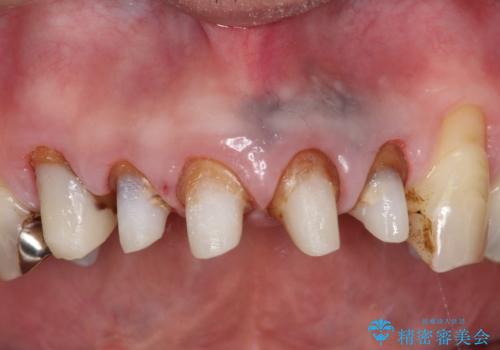

- 上の前歯の根元が黒くなっているので、再治療をしたいとのことで来院された患者様です。

レントゲンを撮影すると、適合不良のかぶせ物が装着されており、根の治療も不十分であることが確認されました。

適合不良のかぶせ物をすべて除去して、根の中の治療から再治療を行うこととなりました。

適合不良のかぶせ物が装着されていた歯は、内部がやはり虫歯になっていました。

かぶせ物だけではなく見えないところも、精密な治療をすることが重要となります。